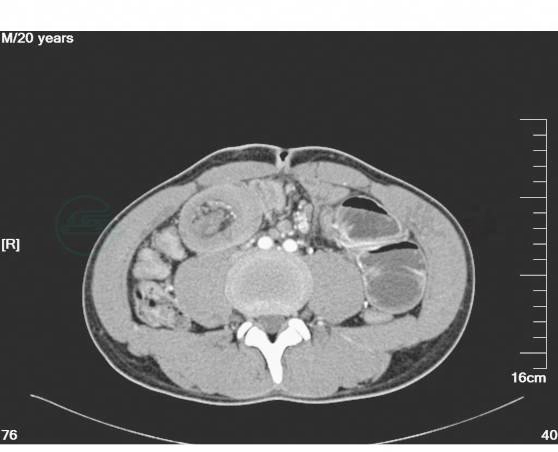

1.收入病房后予禁食水、抗感染、补液、保肝、抑酸、心电监护等对症治疗。密切观察病情。同时完善全腹增强CT、电子纤维结肠镜以进一步明确诊断。完善心电图、心脏彩超、肺功能及其他常规生化检查,以进一步评估患者心肺功能状态、营养状态。全腹增强CT:上腹部空肠肠管扩张,右中下腹靠近回盲部局部可见一软组织密度团块影,内见少量脂肪影,肠壁明显增厚,并见少量水样密度影包绕。结肠肠腔内可见较多肠气影。增强:右中下腹局部肠管管壁增厚、强化,并见管腔内见血管强化影(图3~图7)。

图5 腹部增强CT示局部肠管管壁增厚、强化,并见管腔内见血管影(三)